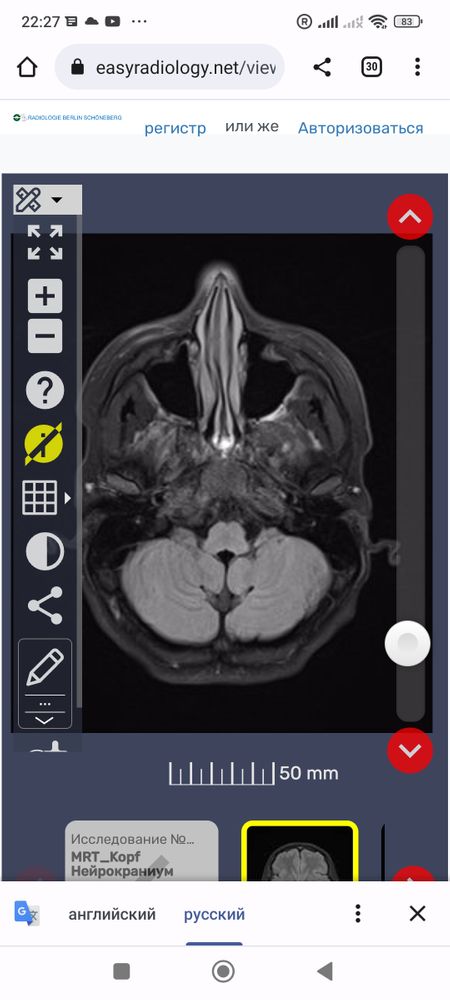

Что это за белые точки вокруг мозга? И все ли впорядке